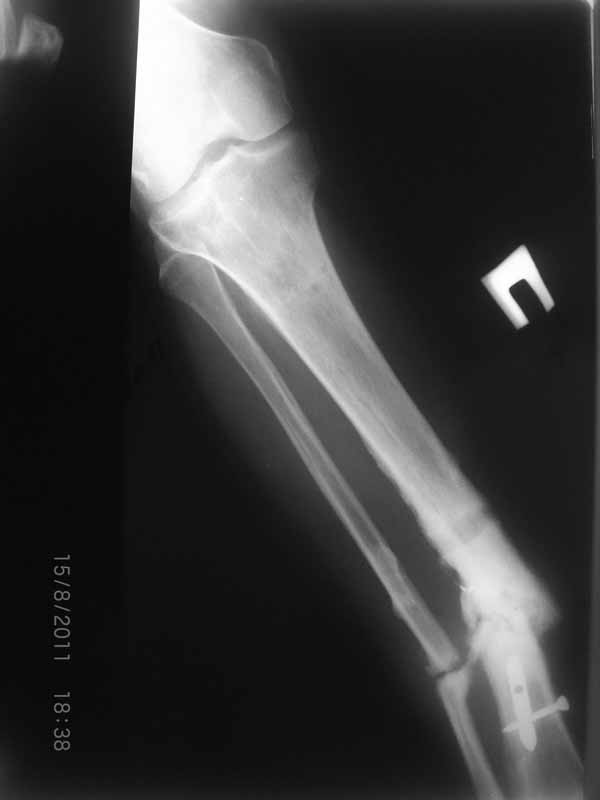

Ivan, mne kazetsia fixacia gvozdem bila ne stabilnaia, gvozd tonkii i korotkii(unreamed nail verno?) Dumau shto kanal nado rassverlit rimerom i postavit novii gvozd, tolstii i dlinii, pridetsia konechno mesto pereloma otkrit, ne zabit takze Bone Graft.

Спасибо за сообщения! Но мне видится что концы отломков большеберцовой кости мертвые. И поэтому мне представляется сомнительным что на гвозде даже с обработкой зоны ложного сустава и костной пластикой что-нибудь срастется. Может я и не прав, но по моему без резекции концов сантиметра на 4 перелом не срастется. Но, опять же, жду советов.

Да уж! Ни один из 3-х оперативных методов предшествующего лечения не был исполнен правильно. Везде был серьезный брак. Хотя любой из методов вполне мог бы и должен был бы привести к сращению,...если бы, да кабы.. В результате имеем то, что имеем. Что делать? Во-первых - подумать. Во-вторых - еще раз подумать. В третьих - еще больше подумать.

Иван, Вам видится зона перелома мертвой, а мне вовсе нет. Есть ли возможность сделать сцинтиграфию с технецием? Это может доказать нежизнеспособность или воспаление концов. Тогда есть резон для такой "крайней" меры как резекция. Есть ли клинические признаки инфекции в области первичной раны?, п\операционных рубцов?, в местах проведения спиц (нет ли спицевого остеомиелита)?.. В общем, вопросов может быть много.

Если нет данных за инфекцию в зоне перелома мы бы аппараптом дозированно устранили деформацию и, не удаляя дистальный фрагмент сломанного гвоздя, закрыто, после рассверливания заштифтовали бы достаточно толстым и надлежащей длины гвоздем.... Если есть спицевой остеомиелит, то также сначала аппарат, затем рассверливанме и цементный спейсор с а\б согласно посевам, через 2-3 недели удалить спейсор, повторно рассверлить и заштифтовать штифтом, возможно покрытым антибиотиком. А если Вы умело владеете техникой Илизарова, и больной согласен, можете оставить аппарат как окончательный метод фиксации....

В любом случае, если нет инфекции в зоне несращения и кость жизнеспособна, упаси Вас Бог что либо открывать и добавлять свободную костную пластику. Надо попытаться все сделать закрыто. Если откроете, то через пару месяцев, а может и раньше, все закончится резекцией и значительно большей чем 4 см...

Если там инфекция, что не исключено, судя по представленным данным, то вариантов нет - резекция в пределах здоровой кости.